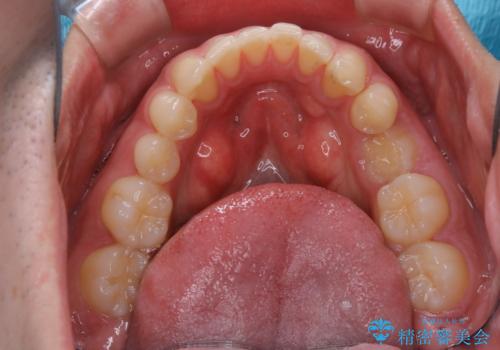

親知らずを抜いて1週間後にPMTC 歯のクリーニング

- 親知らずの抜歯後の約1週間後に抜糸(縫った部分の糸とり)で来院されました。その際、抜歯後は傷口が怖くて歯磨きが上手くできず、汚れや口臭が気になるためクリーニングも希望されました。

抜歯後は多少出血したり、違和感や痛みを感じたりすることがあります。そのため親知らずを抜いたり、外科的な処置をするといつも通りの歯磨きがしづらくなります。また、傷口の周りが心配で、歯ブラシをするのが怖くなるものです。抜歯後落ち着いたら、歯科医院にて専門の機械を使用しクリーニングをすることがおすすめです。抜歯前や後にPMTCを行うことで、お口の中の健康維持につながり、その後の感染・腫れ・口臭予防などになります。

親知らず抜歯後正常に治癒が進んでいれば1週間後から可能です。